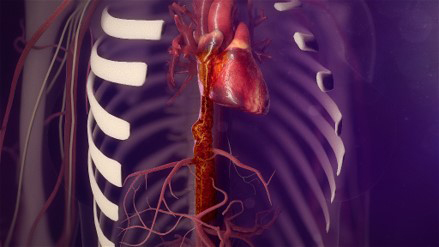

A scan found a 9-centimeter tumor thrombus, or fingerlike extension, growing from Jessica's inferior vena cava, the largest vein in the body that comes out of the back of the heart. The inferior vena cava brings blood from the lower body, pelvis and abdomen to the heart to be pumped into the lungs for oxygenation.

Because the tumor was growing into Jessica's heart, her team had to put Jessica on cardiopulmonary bypass. A machine temporarily took over the function of her heart and lungs, circulating blood and oxygen throughout her body during the surgery.

The inferior vena cava extends down into the liver. The tumor thrombus was "sticking its tongue" into the liver veins from the heart. To access the tumor in the inferior vena cava, Dr. Caicedo had to mobilize the liver and hold it outside of Jessica's body so that the team could access the tumor in her inferior vena cava. Dr. Kundu had to do the same with the kidneys. To do this, they also had to mobilize the retroperitoneum, the tissue that lines the abdominal walls and holds most abdominal organs in place. Dr. Caicedo helped "milk" the tumor thrombus out of the veins in the liver, being careful not to break off any clotting factors.

Step 3: Control the Vena Cava

Dr. Eskandari clamped Jessica's vena cava at the top. With the lower part of the tumor completely freed from the liver, the team carefully cut Jessica's vena cava in half and pulled the tumor out of it from below. They reconstructed her vena cava with a prosthetic vein made out of Gore-Tex® that Jessica will always have.